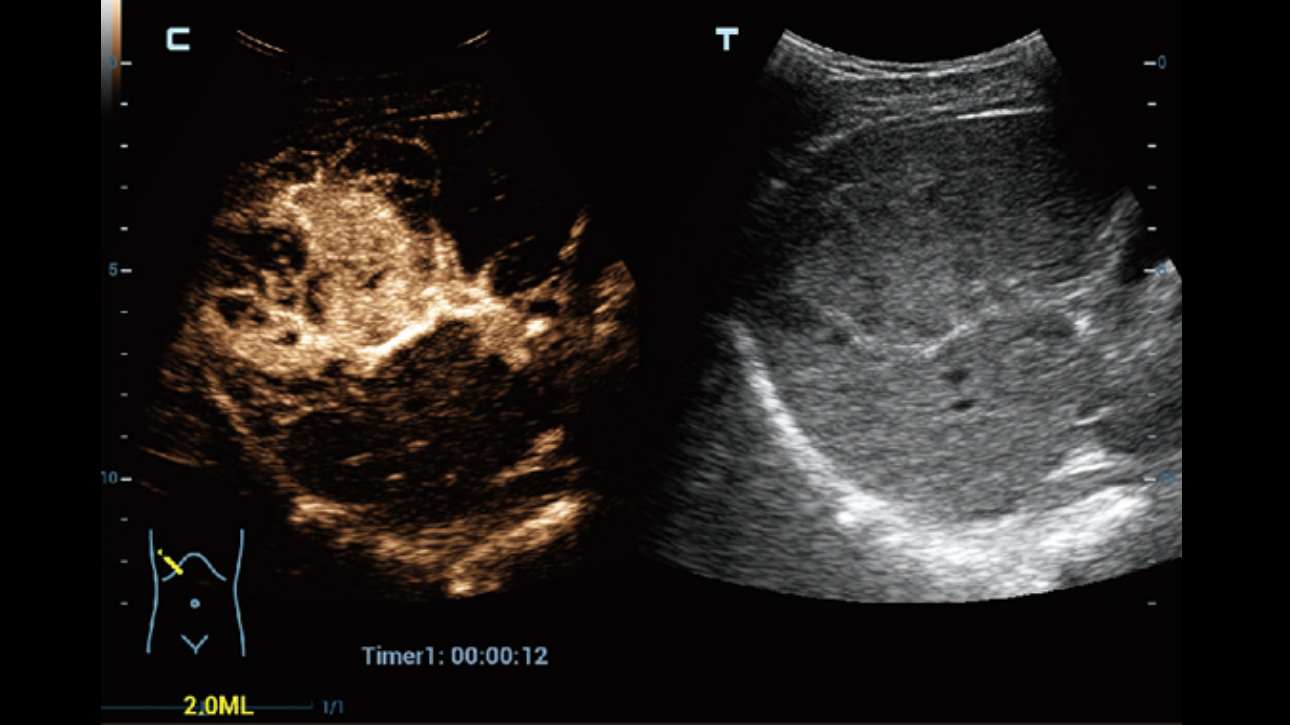

Channel data based ZST+ provides Enhanced Channel Data Processing for greatly improved imaging clarity. By multiple and retrospective channel data processing, it makes the best use of acoustic information for image improvement.

HD Scope: By processing channel data retrospectively, HD Scope enables tissue-specific enhancement with improved detailed information and image contrast on specific region of interest.